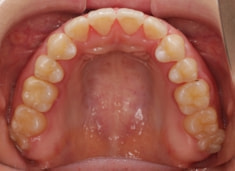

治療前